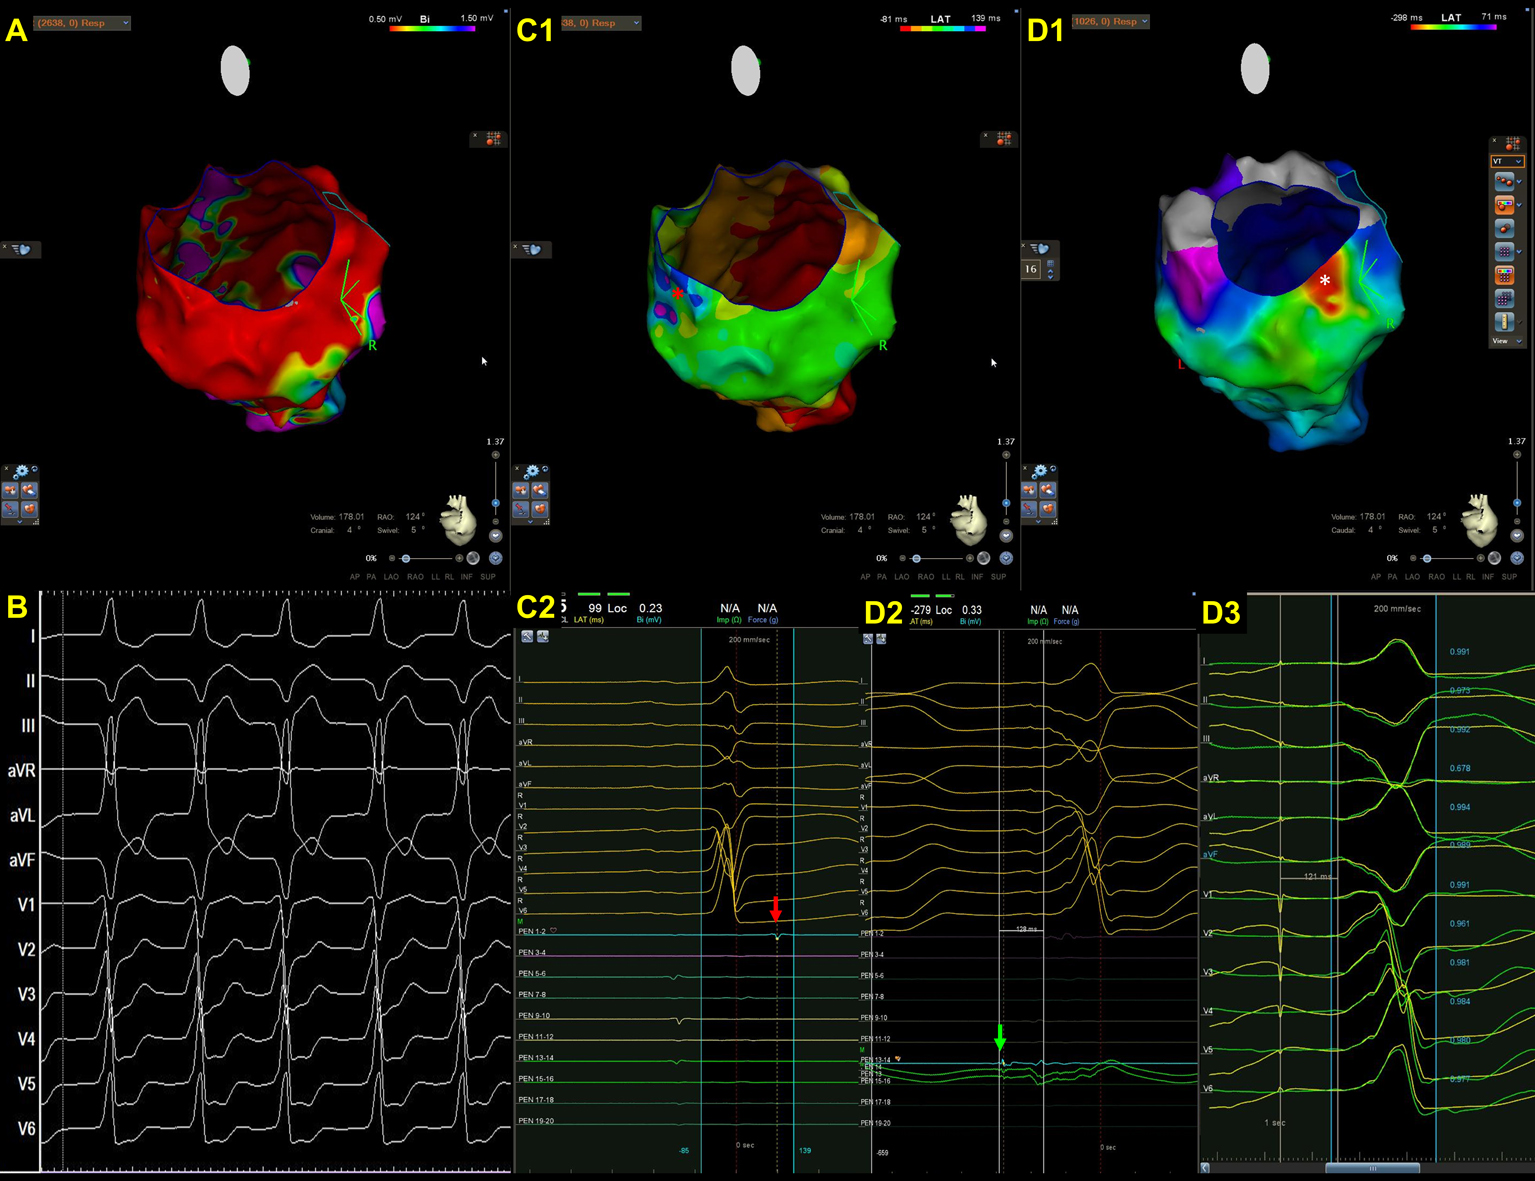

Fig. 2.A representative case of focal VT in a patient with cardiac sarcoidosis. (A) An endocardial bipolar voltage map showed extensive scarring of the LV septum and inferior wall. (B) The spontaneous VT was characterized by a left bundle branch block pattern and superior axis. Wobbling of the VT cycle lengths was also noted. (C1–2) An isochronal late activation map (C1) was created by annotating the latest component of a bipolar electrogram. At the basal inferior portion of LV, there was an isochronal crowding region. (C2) The red asterisks indicate an isolated late potential (red arrow in C1) (D1–3). VT activation map (D1), the earliest electrogram during VT mapping (D2), and pacemapping at the earliest activation site (D3). The VT activation maps (D1, from red, orange, yellow, green, blue, indigo, to violet). Contrary to the majority of scar-related VTs, there was a centrifugal pattern of activation in this patient, indicating that the mechanism of VT in this case was focal rather than macroreentrant. There was a very early prepotential (D2, green arrow) preceding the onset of VT by 128 ms in the white asterisks area (D1) where was adjacent to the isochronal crowding region. During pacemapping, the QRS morphology at the earliest activation point was 96% similar to that of clinical VT. There was also a significant delay between the stimulus and QRS onset (121 ms) during pacemapping. The VT was terminated by ablation at this site.

Cardiac sarcoidosis can affect RV, LV, or both [35, 36, 37, 38]. Patchy scarring is most often observed in the septum, followed by the anterior wall, the LV outflow tract, the inferior wall, the lateral wall, and the apex within the mid-myocardial and subepicardial layers of the LV, whereas scarring is generally seen in the RV [35, 36]. In addition, since the basal septum is frequently involved, right septal VTs, peritricuspid/perimitral VTs, or VTs originating from the Purkinje system are also common [37, 39]. A representative case was shown in Fig. 2.